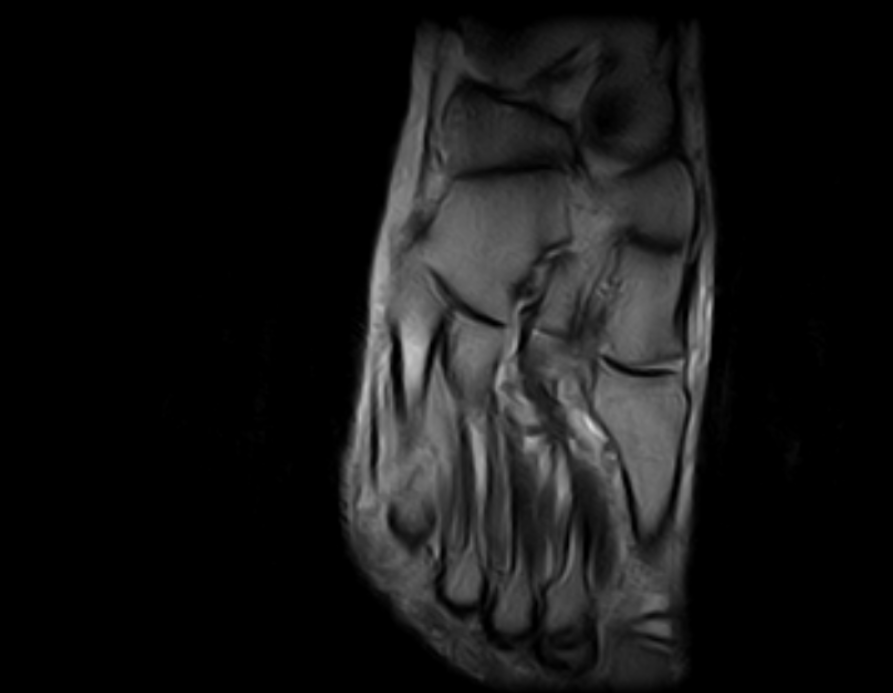

Imágenes Clínicas

El S-scan permite resonancias magnéticas cerebrales gracias a su amplia gama de aplicaciones a través de bobinas dedicadas.